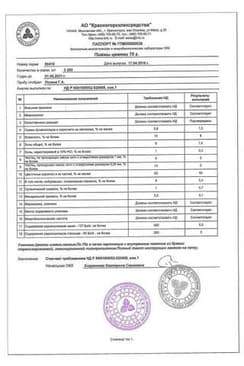

Сертификаты

Сертификаты